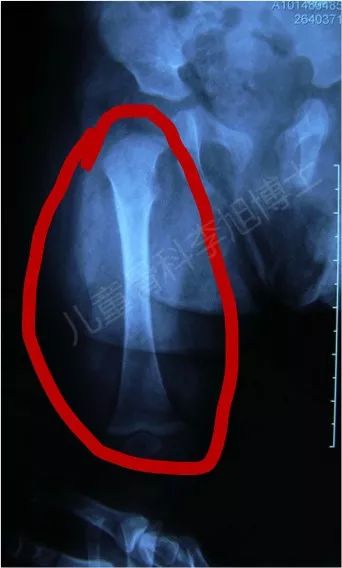

现在大家再看一下我们之前治疗过的产伤病例:

孩子出生时发现股骨干骨折

佩戴Pavlik吊带两周后,骨折已初步愈合,大量骨痂形成

孩子5个月龄时复查,塑形完成